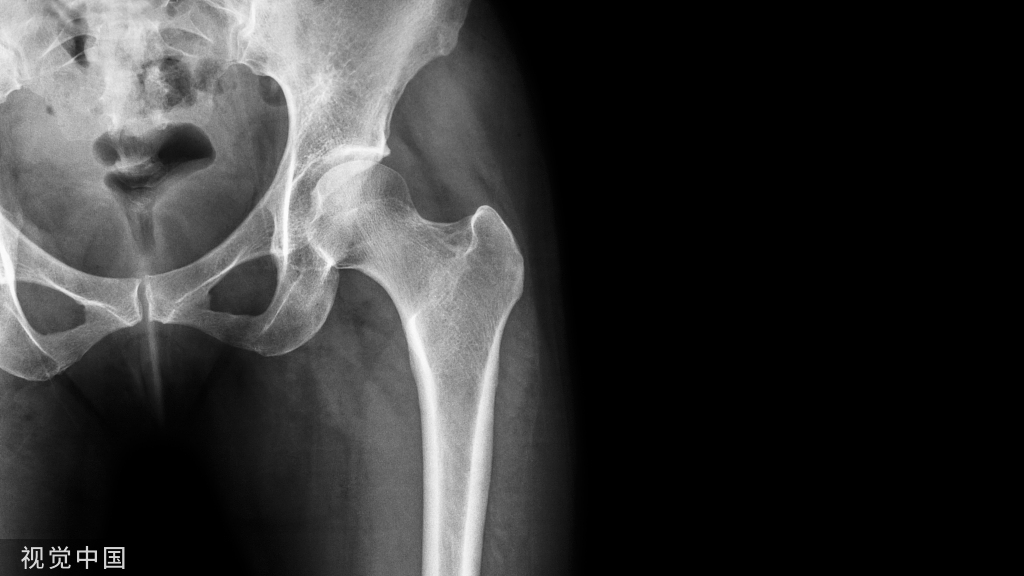

对于胫骨近端骨折,无论是髌上还是髌下入路,主钉置入后骨折成角问题不可避免,术后对线不良率依旧较高。使得部分学者坚持使用钢板固定此类型骨折。

胫骨骨折通常为高能量损伤,髓内钉治疗胫骨骨折具有创伤小、允许早期负重等优点,已逐渐成为胫骨干骨折治疗的金标准。然后对于胫骨近端骨折,无论是髌上还是髌下入路,主钉置入后骨折成角问题不可避免,术后对线不良率依旧较高。使得部分学者坚持使用钢板固定此类型骨折。